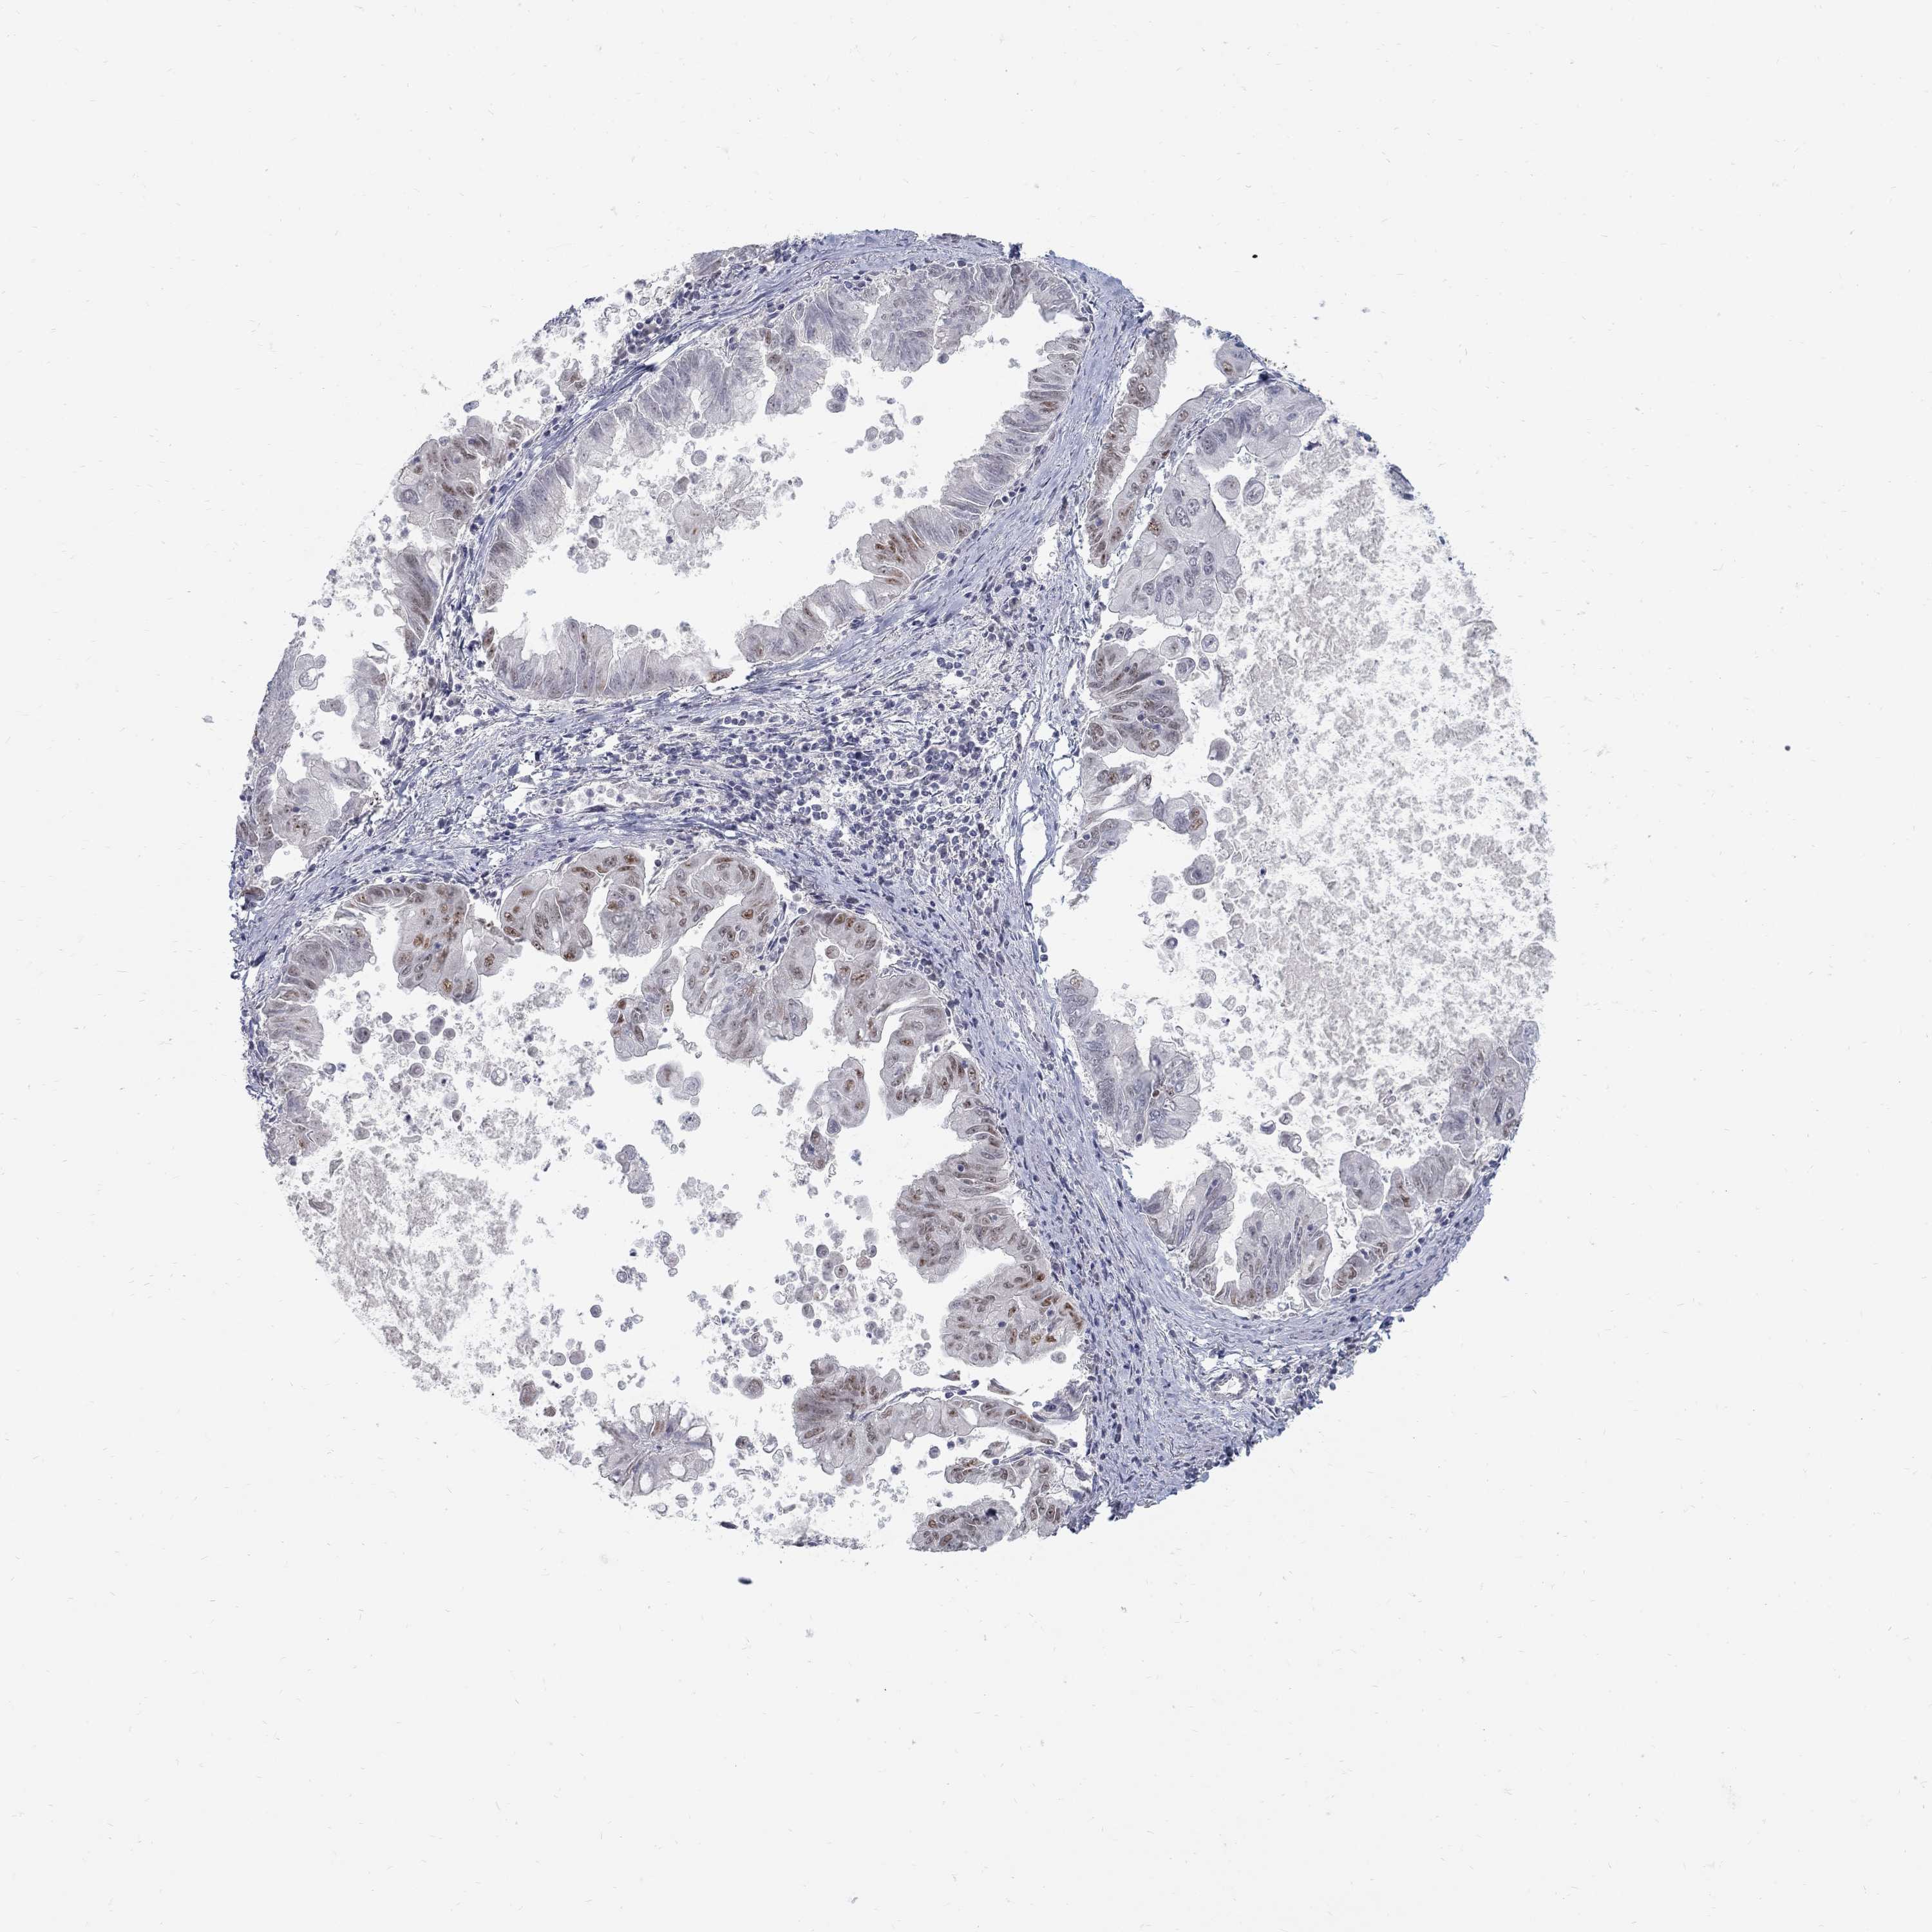

STOMACH CANCER - Protein expressioni

A mouse-over function shows sample information and annotation data. Click on an image to view it in a full screen mode. Samples can be filtered based on level of antibody staining by selecting one or several of the following categories: high, medium, low and not detected. The assay and annotation is described here.

Note that samples used for immunohistochemistry by the Human Protein Atlas do not correspond to samples in the TCGA dataset.

Antibody stainingi

Antibody staining in the annotated cell types in the current human tissue is reported as not detected, low, medium, or high, based on conventional immunohistochemistry profiling in selected tissues. This score is based on the combination of the staining intensity and fraction of stained cells.

Each image is clickable and will lead to virtual microscopy that enables deeper exploration of all samples and also displays staining intensity scores, fraction scores and subcellular localization as well as patient and tissue information for each sample.

Antibody HPA077882

Staining

High

Medium

Low

Not detected

Intensity

Strong

Moderate

Weak

Negative

Quantity

>75%

75%-25%

<25%

None

Location

Nuclear

Cytoplasmic/membranous

Cytoplasmic/membranous,nuclear

Adenocarcinoma, NOS